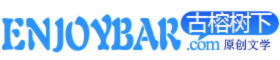

遗憾的是,小闻的右眼已经完全失明,但左眼还能通过手术恢复视力,需要立即进行,玻璃体切除手术治疗,糖尿病性视网膜病变早期没有任何不适症状,发展到一定程度后,会引发玻璃体积血,牵拉视网膜脱离,患者视力会急剧下降甚至失明。

眼科主任主任医师朱冬梅提醒:一旦得了糖尿病,失明概率是正常人的25倍!糖尿病是一种代谢性疾病,看起来似乎与眼睛,没有太大的关系,实际上糖尿病的并发症,可怕到令人发指。糖尿病患者失明的概率是正常人的25倍,是名副其实的"光明杀手"。

有研究统计:中国有近1.3亿的糖尿病患者,这其中约有30%,患有糖尿病视网膜病变,这其中又有超过1000万人面临失明的威胁。可以这样说,几乎所有的眼病,都可能发生在糖尿病患者身上。

比如说视网膜病变、白内障、眼外肌麻痹等,其中,视网膜病变最为常见,晚期可导致玻璃体出血、视网膜脱离而失明。

怎么才能避免中招?不是夸张,糖尿病性眼病就像"温水煮青蛙",很多人一开始都没什么感觉,等到眼睛看不见后,才想到要去看眼科,那时可能就晚了!所以,糖尿病患者定期去医院检查眼睛真的很重要!